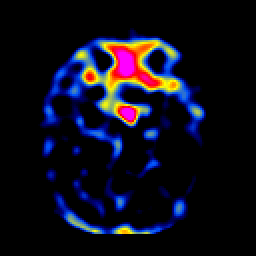

SPECT TL Study #1 -- Slice #18

[Home][Help][Clinical][Tour 1][Tour 2][Tour 3] Slice 18